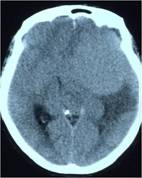

经查体,神经外六科吴杰主任诊断为:左侧蝶骨嵴占位性病变,考虑脑膜瘤可能性大。之后黄女士完善了相关检查,颅脑CT及CTA检查提示:左侧中颅窝底巨大占位病变,其内血管丰富,临近左侧大脑中动脉明显受压向上移位,考虑脑膜瘤;颅脑磁共振提示:左侧前中颅窝底巨大占位性病变,考虑脑膜瘤。介入栓塞提示:肿瘤主要由左侧脑膜中动脉额支、少量由左侧眼动脉脑膜支参与供血。

颅脑CT及CTA检查可见左侧额颞稍高密度占位,肿瘤血供丰富